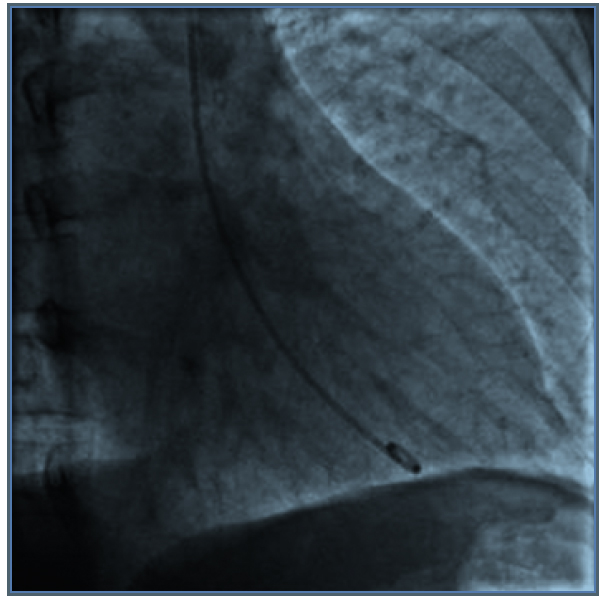

Consultó en urgencia por cuadro de dolor retroesternal de inicio agudo, opresivo, irradiado a dorso, diaforesis y palpitaciones. A su ingreso destaca: presión arterial (PA) 214/120 mmHg, frecuencia cardiaca (FC) 126 x min, mala perfusión, somnolencia y manchas café con leche. Las enzimas cardiacas mostraron valores normales. El ECG reveló supradesnivel de ST y T negativas de V2 a V4, con Q patológica en V5-V6-DI y AVL. Coronariografía: Coronarias sin lesiones, hipokinesia difusa con fracción de eyección (FE) de 20%. Interpretándose como miocardiopatía de Takotsubo (MTT) (Figura 1). En base a los hallazgos con alta sospecha de feocromocitoma, se solicita metanefrinas urinarias totales: 6,3 mg/24 h (VN: 0-1), TSH 2,32 uIU/ml PTH: 46,1 pg/ml Ca 9,5 mg/ dl, P: 4 mg/dl, Alb: 4,3g/dl Calcitonina basal: 4,8 pg/ml (VN: < 4). Ecografía renal descartó estenosis de arterias renales con masa renal sugerente de neoplasia. TC con contraste: masa suprarrenal derecha de 6,3 cm de eje mayor con características de feocromocitoma (Figura 2).

Figura 1. Coronariografía: Coronarias sin lesiones.